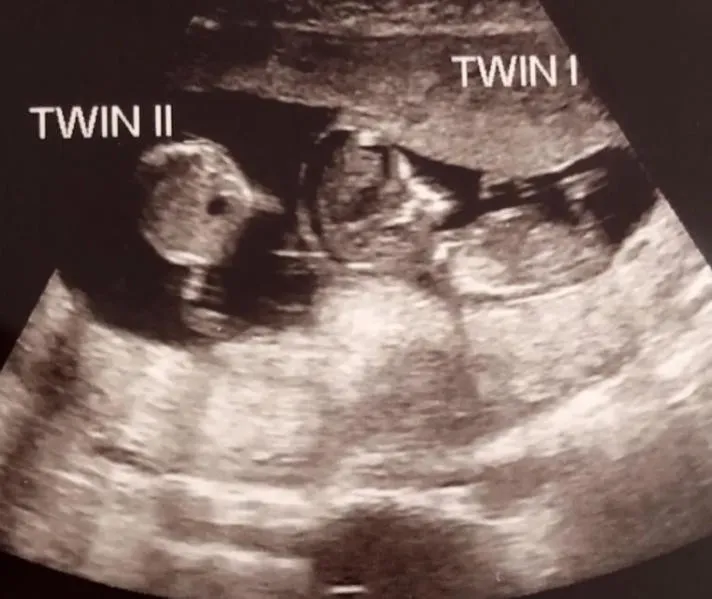

El médico dio noticias confusas.

Estaba embarazada de gemelos.

Sin embargo, un feto era notablemente más pequeño y parecía tener aproximadamente una semana menos.